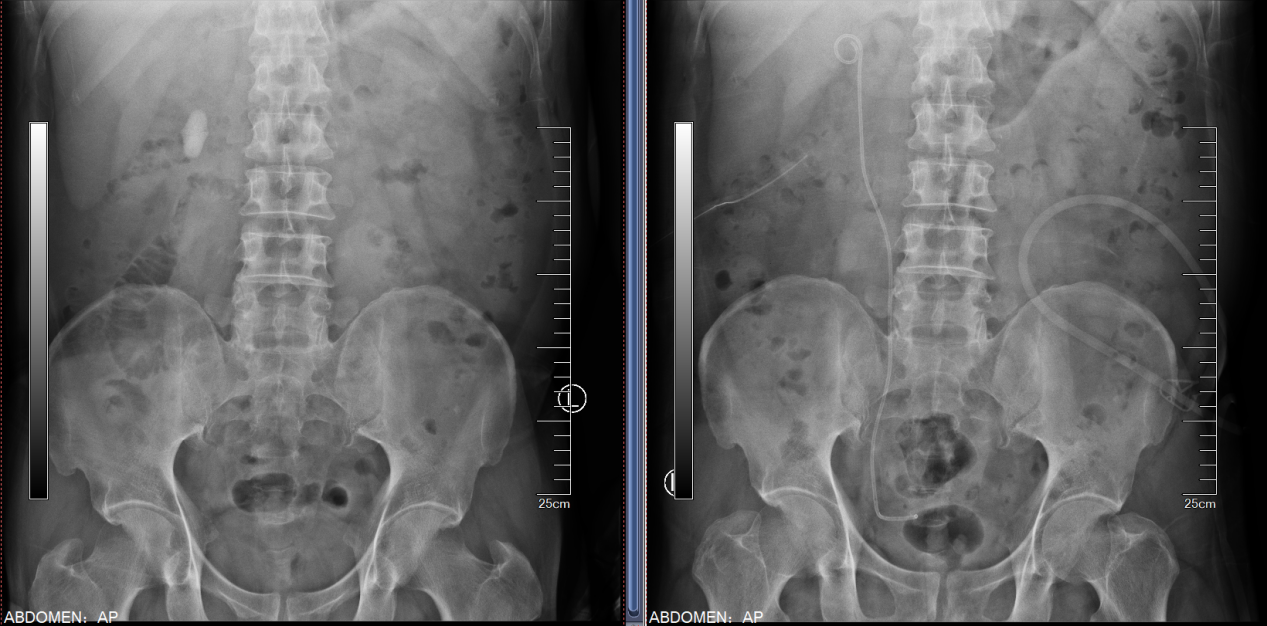

患者双肾结石多年,既往有多次结石手术病史,因为右腰部疼痛入院,检查后发现患者双肾多发结石。左侧为完全“鹿角型”结石,结石充满了整个肾脏,右侧输尿管也有多颗结石。浦金贤主任指出,患者双肾结石负荷大,左侧尤甚,且合并右侧输尿管结石,手术难度大,风险高,需优先保护肾脏功能,解除梗阻,尽可能彻底清除结石,减少术后再发概率。

经过科室讨论,周守军主任决定以分期手术的方式,借助智能控压清石系统,通过输尿管软镜处理右侧肾及输尿管结石。而对于左侧的无积水完全“鹿角型”结石,周主任在手术过程中一期采用标准通道经皮肾镜,结合第五代EMS超声弹道碎石系统清除结石主体,二期通过输尿管软镜配合末端可弯曲负压吸引鞘清除残余结石。术后患者恢复迅速,解决了困扰多年的结石问题。